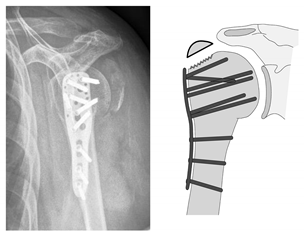

| Complication Type | Exemplary Images by X-rays or Pattern Images | Definition |

|---|---|---|

| 3 | ![]() | Type 3 describes a displacement of the angular stable plate osteosynthesis with screw cutout/fracture avulsion in the humeral shaft region, while the humeral head position remains intact. |

| 4 | ![]() | Complication Type 4a is based on the presence of AVN of the humeral head without concomitant destruction of the glenoid articular surface due to an associated screw cutout through the humeral head cortex. |